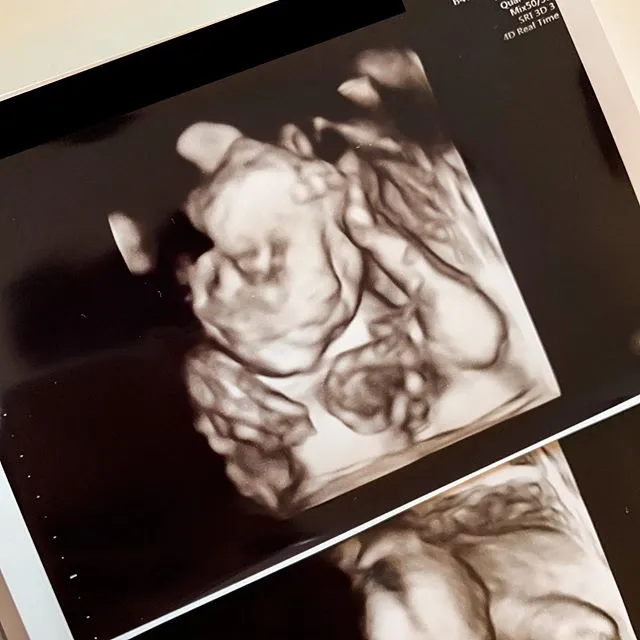

Kapanlagi.com - Sebuah kabar bahagia baru saja datang dari Marissa Nasution. Aktris cantik berdarah Jerman - Batak ini mengumumkan jika saat ini ia tengah hamil anak kedua. Hal itulah yang bisa kamu temukan dalam postingannya di Instagram.

Pengumuman kehamilan Marissa Nasution ini diunggah dengan memamerkan hasil foto USG. Di sana kamu bisa melihat dengan jelas janin dalam perutnya yang tumbuh dengan sempurna. Penasaran seperti apa penampakannya?

Lihat saja seperti apa penampakan janin dalam kandungan Marissa Nasution yang tampak jelas dalam foto di atas. Bersamaan dengan unggahan tersebut, ia pun menuliskan caption yang berbunyi, "Selamat pagi, udah kelihatan si hidung mancung. Boy or Girl? Subscribe ke vlognya Allie ya aunties and uncles (LINK IN BIO)."